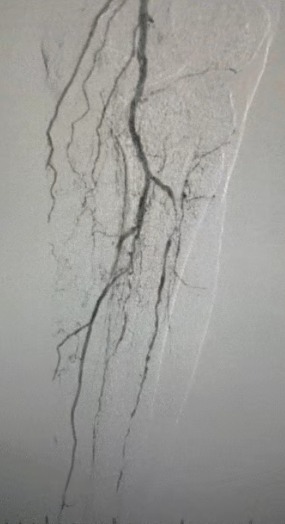

· Badanie fizykalne: słabe pulsy udowe; brak pulsów podkolanowych i grzbietu pedis; owrzodzenie lewego pierwszego palca; martwica prawego pierwszego i drugiego palca

· Obrazowanie przedoperacyjne: Ciężkie, rozproszone zwapniałe zwężenie w obustronnych tętnicach kończyn dolnych

Biorąc pod uwagę złożony stan naczyniowy, wybraliśmy system cewnika dylatacji balonowej ThorCrack Peripheral IVL. Ze względu na ograniczoną tolerancję pacjenta wykonano etapowe zabiegi interwencyjne na obu kończynach dolnych.

Wynik chirurgiczny

Po zabiegu znacznie poprawiło się zwężenie tętnic, zwiększył się przepływ krwi i wzrosła temperatura skóry. Nie wystąpiły powikłania pooperacyjne. Zarówno pacjent, jak i zespół chirurgiczny byli bardzo zadowoleni z wyników.